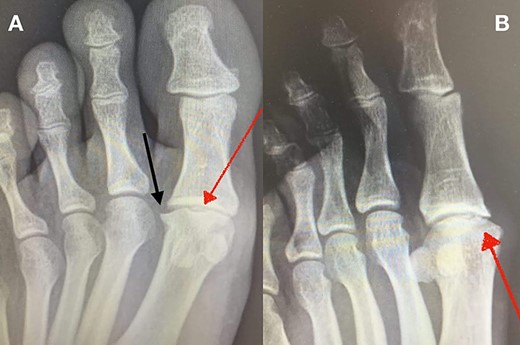

MRI of the left foot, shows low signal intensity lesion on the MH. The red dots show the depth of a subchondral cyst formation.

Standing anteroposterior (AP), oblique and lateral radiographs of the affected foot were taken. On the AP and oblique views, an OD lesion of the 1st MH was visible (lytic lesion of the subchondral bone and subchondral sclerosis formation) with a lateral-forming osteophyte (Fig. 1A and B). Magnetic resonance imaging (MRI) of the left foot clearly shows the osteochondral defect of the 1st MH (Figs 2 and 3).